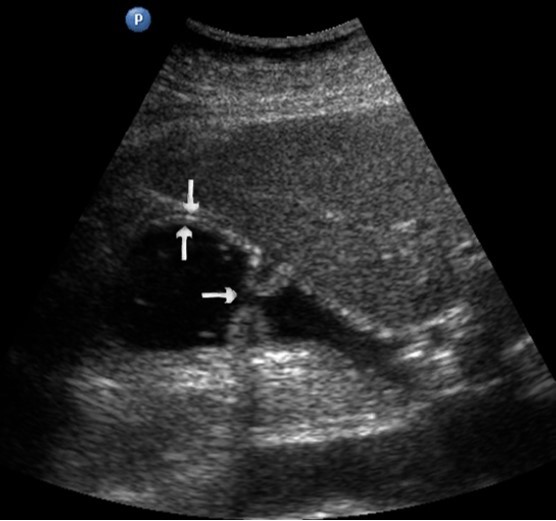

T3 stage of polypoid form was recorded in one case, ulcerative form – in 11 cases, infiltrative ulcerative forms – in 21 cases and diffused infiltrative forms – in 8 cases. The Sonographic features of infiltrative ulcerative form of gastric carcinoma was shown as local uneven thickening of the stomach wall with a length of up to several centimeters with intermittent images and ulceration of the mucosa (Figure 11). The Ulcerative form of gastric carcinoma was shown as a raised margins surrounded by a thickened gastric wall with irregular margins (Figure 12). Gastric carcinomas of diffuse infiltrative form is illustrated as a diffuse thickening of the muscle layer, a smooth contour, discontinuous mucosal image without ulceration and involvement of the serous membrane in the process (Figure 13).

Figure 13.Gastric carcinomas of diffuse infiltrative form in the posterior wall of the stomach body of stage T3. The tumor is manifested by diffuse thickening of the muscle layer, a smooth contour, discontinuous mucosal image without ulceration and involvement of the serous membrane in the process. An enlarged, altered lymph node of low echogenicity, round shape, without differentiation of the peripheral and central part, is visualized behind the stomach.